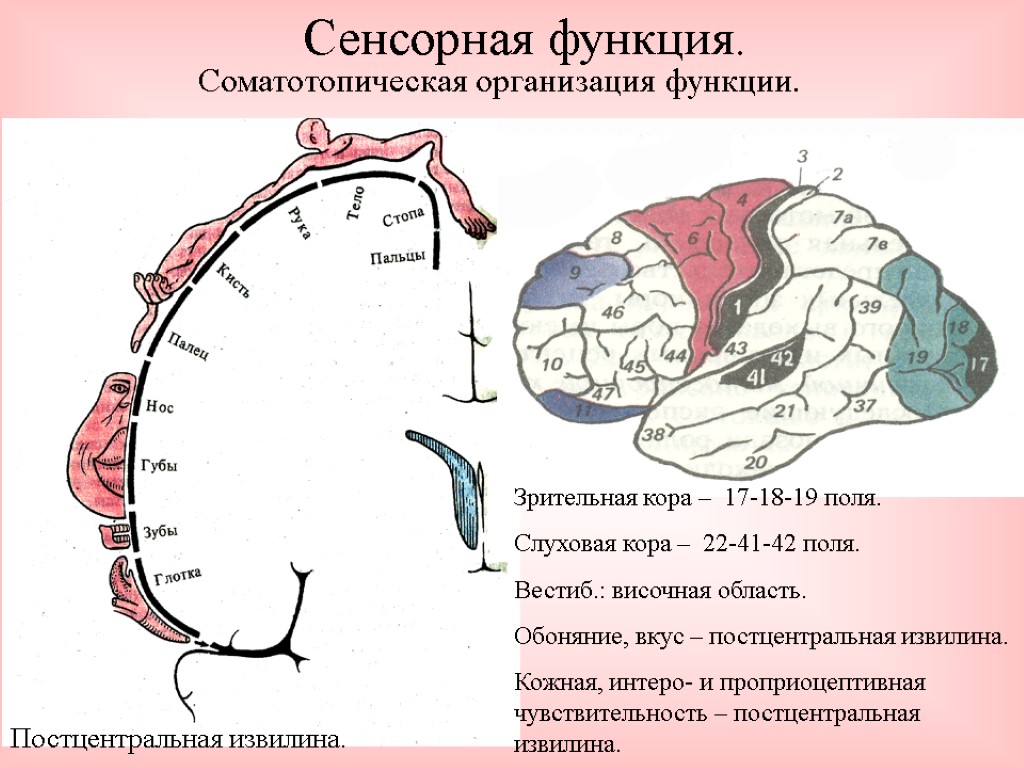

Схема чувствительных зон новой коры мозга